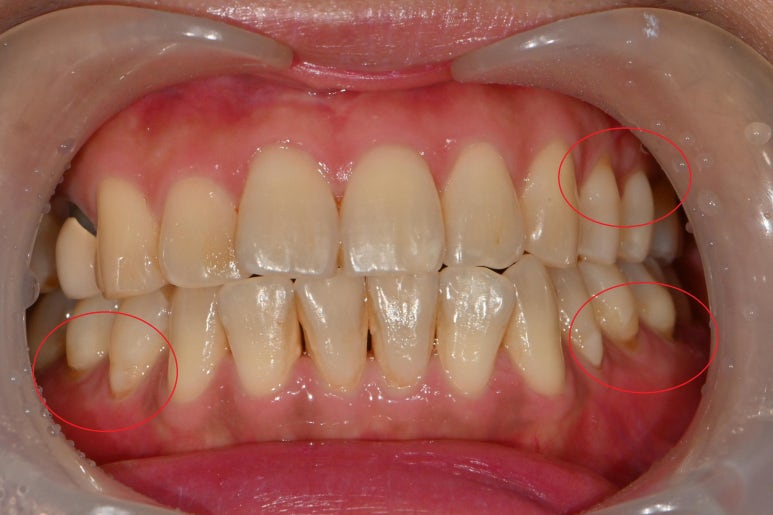

오늘 소개할 증례는 치경부 마모증입니다.

치경부 마모증이란 치아의 목 부분이 마모된다는 것입니다.

치경부 마모증의 원인은 씹는힘이 강하거나,

양치를 너무 강하게 하거나

치열이 고르지 않을때 많이 생깁니다.

다음 사진으로 어떤식으로 치료하는지 보여드리겠습니다.